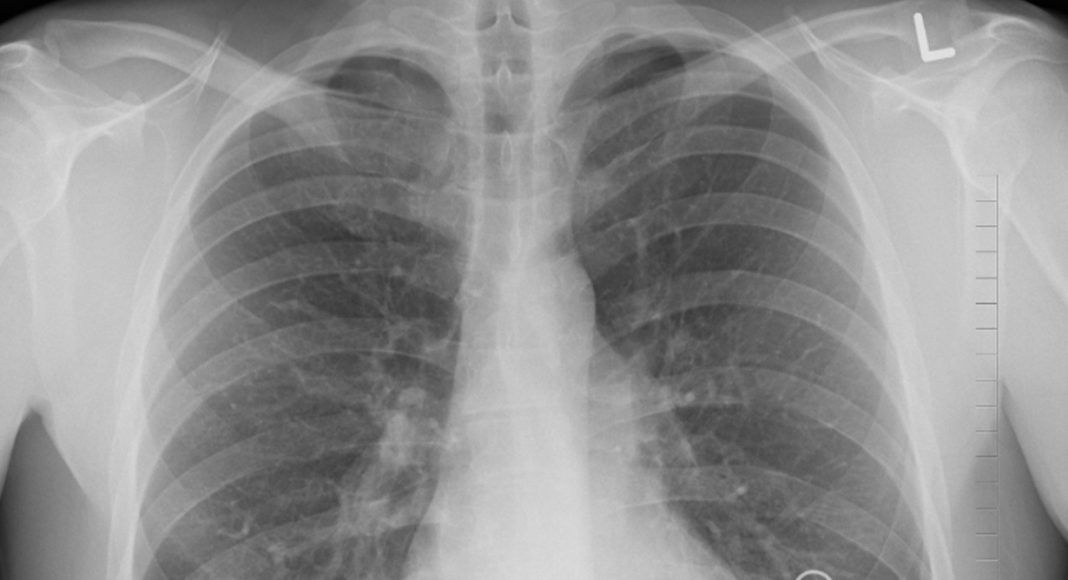

Акция направлена на раннее выявление заболеваний лёгких и повышение осведомлённости населения о важности регулярных медицинских проверок. Жителям Хакасии настоятельно рекомендуется воспользоваться этой возможностью для профилактики и своевременной диагностики инфекционных заболеваний.